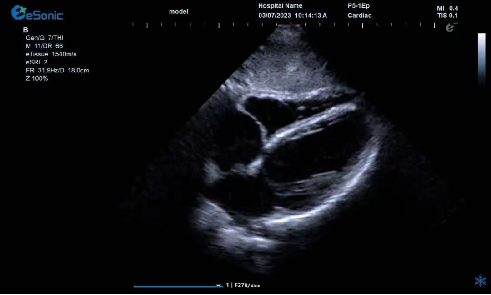

临床病例(三)

二尖瓣病变,脱垂?三叶?